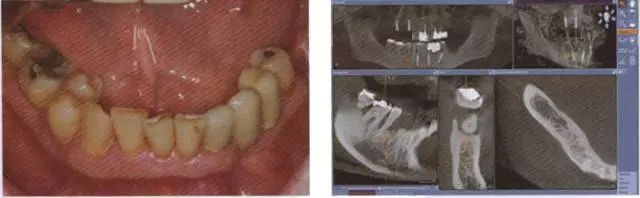

在口腔外科治療中, 拔牙后疼痛是最常見的并發(fā)癥,其成因有很多種因素5。通過拔牙造成牙糟骨創(chuàng)傷的因素, 除了患者特定因素外, 其它的還有如一般健康狀況、藥物、尼古丁和酒精5,15。由于感染調(diào)節(jié),使細(xì)菌滲透到牙糟骨內(nèi)并形成骨炎,其中患者會因由此所造成的神經(jīng)炎而產(chǎn)生強(qiáng)烈的癥狀。在序列拔牙中, 術(shù)后疼痛的出現(xiàn)與單顆牙拔除相比卻鮮有被報道15。然而在即刻種植后, 這可能會因患者要求拔出種植體而導(dǎo)致產(chǎn)生劇烈的疼痛; 或者在另一方面會顯示, 造成種植體底端出現(xiàn)種植體周圍炎癥狀。如果出現(xiàn)這樣的情況,是非常難以治療的,因?yàn)楦腥镜牟≡钔ǔN挥谏鄠?cè),而通過外科手段進(jìn)入骨溶解區(qū)兒乎是不可能的(圖1至7)。

圖1 圖2

圖1 患者46牙根管再治療失敗,出現(xiàn)根尖炎癥,準(zhǔn)備拔除做即刻種植

圖2 小視野CBCT圖像顯示種植修復(fù)一年后的骨容解情況